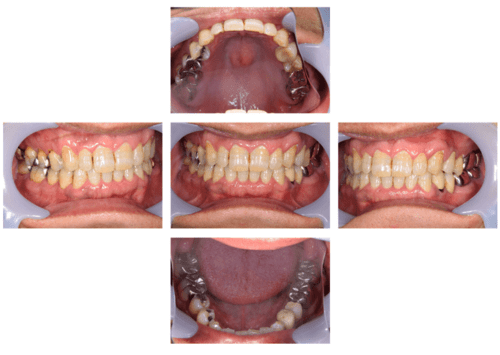

口腔内写真

- Befor

- After

| 年齢 | 50代・男性 |

|---|---|

| 主訴 | 左上7番 左下5番7番 |

| 治療内容 | ・インプラント埋入 ※1:GBR(骨造成)・・・骨再生誘導法。骨の高さや厚みを人工骨や人工膜などを使用し再生する方法 |

| 治療費 | 合計:1,809,500円(税込) ■内訳 ・左上7番 ・左下5番7番 |

| 治療期間 | 左上7番約1年 左下5番7番約10ヵ月 |

| 治療方針 | 左上7番は昔他院で被せものをしており、被せものの中が歯ぐきの中まで虫歯になっていたため抜歯せざるを得ない状態だった。抜歯と同時に骨造成を行い、骨が出来るまで4ヵ月待ってからインプラントを埋入した。 ※2ポンティック・・・歯のない部分を補うダミーの歯。 |

| 担当者所見 | 元々金属の被せものが多く入っていたため、2次カリエス※3が多かった。今回は金属ではなく、ジルコニアを使用し、2次カリエスにならないよう、患者様にはブラッシング指導とメンテナンスの重要性をお伝えした。 ※3二次カリエス・・・詰め物や被せものを入れた歯が虫歯になること。 |